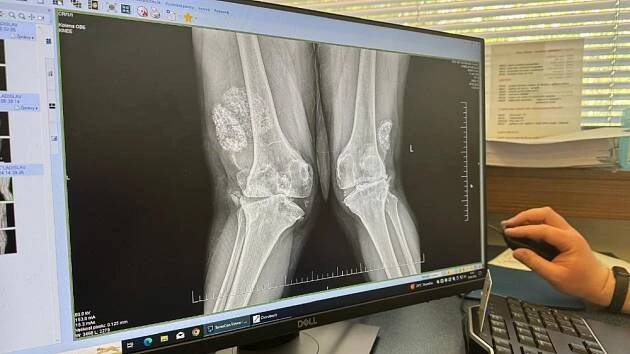

Ladislav Chmelík výměna kolenního kloubu

Výměna kolenního kloubu měla Láďovi z Prahy pomoci. Dnes má vážné následky